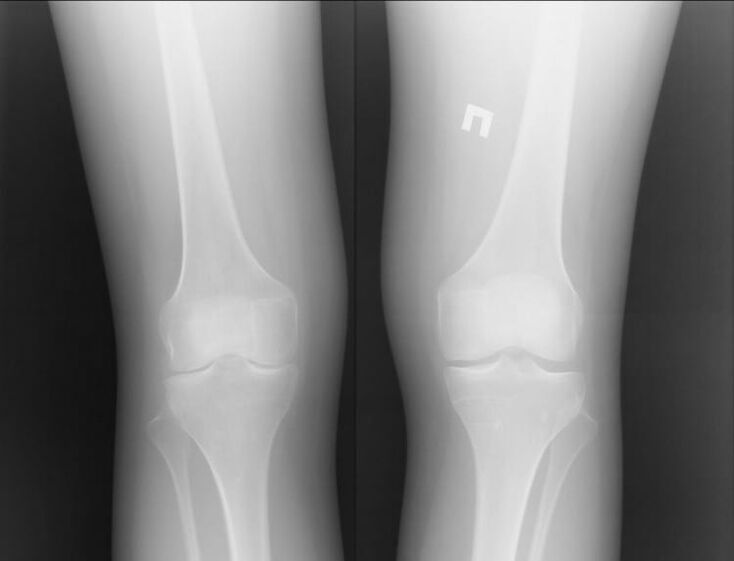

Of course, both diseases are quite serious and it is difficult to say who is worse.However, we can look at the example of a problem in the knee joint.With arthritis, that is, in inflammatory processes, the patient can be assisted.